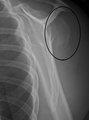

A fracture of the greater tubercle of the humerus

Fracture of the greater tubercle of the humerus